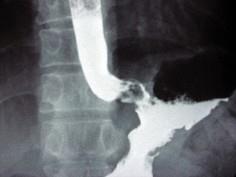

问题 男,56岁,胸骨后不适3月,吞咽时异物感,X线检查如图,最可能的诊断是()

选项 A.食道癌 B.食道腺瘤 C.贲门腺癌 D.胃癌 E.食道下段溃疡

答案 C